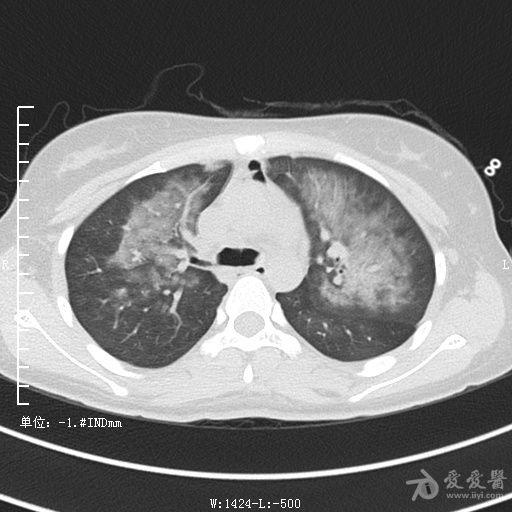

典型支气管扩张及肺水肿CT片

典型支气管扩张肺水肿